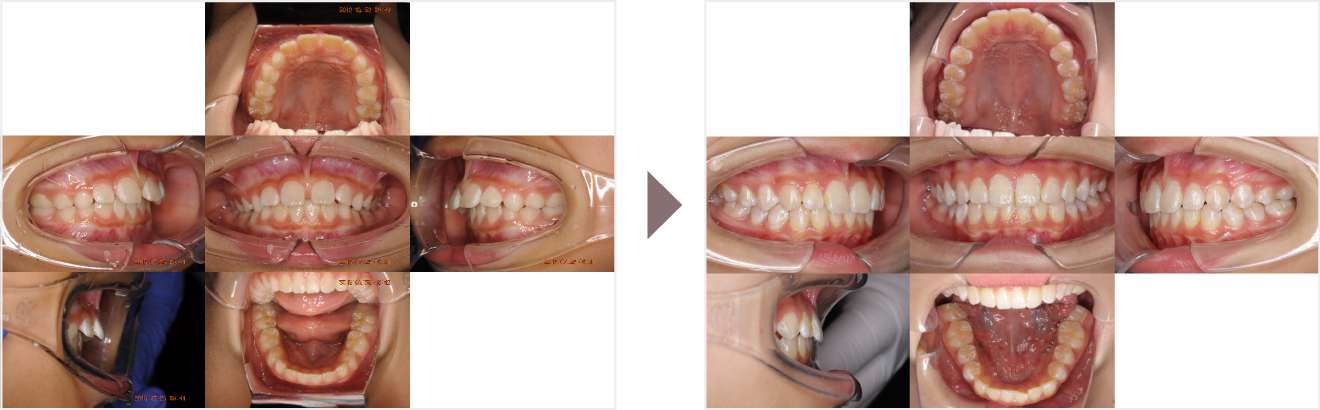

症例叢生

性別

期間8年8ヶ月

治療内容N-Bimler装置、Neo-Capを使用して治療

治療における

副作用・リスク

装着しないと効果は出ません

金額ビムラー装置:550,000円

ネオキャップ:4本

合計:572,000円